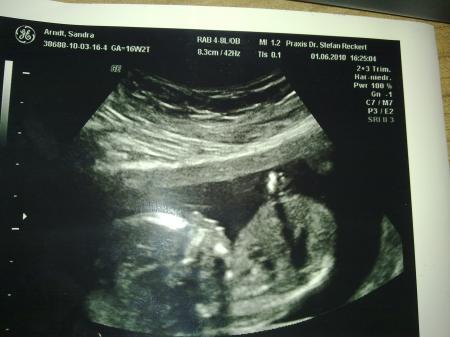

so,wie irina schon so lieb berichtete wird es wahrscheinlich ein kleines super süßes gesundes geliebtes bezauberndes glückliches baby mädchen. nach meinem traum,obwohl ich immer eher einen amerikanischen vornamen wie emily oder sonstwas haben wollte,soll unser schatz emma joy heißen. einen rosa strampler haben wir gekauft-aus optimistischen gründen....hoffe mein fa irrt sich nicht...ach und wenn-egal. die kleine war extrem wild und schlug um sich,trat aus und pinkelte los.lach ach ganz die mama....die kleine pipi emma. organe sind super..herz prima und durchblutung 1a.freu anbei 3 fotos.

noch eins

ja,hat man gesehen das sie pipi gemacht hat.der arzt sagte nur:oh sie macht pipi und dann sah man es.lach sind keine 2 verschiedenen ultraschallgeräte-einfach auf 3d umgeschaltet.mein fa hat wohl mit die neuesten und bestem geräte.dafür ist er wohl auch bekannt-er ist ja auch spezialist für risikoschwangerschaften usw... lg